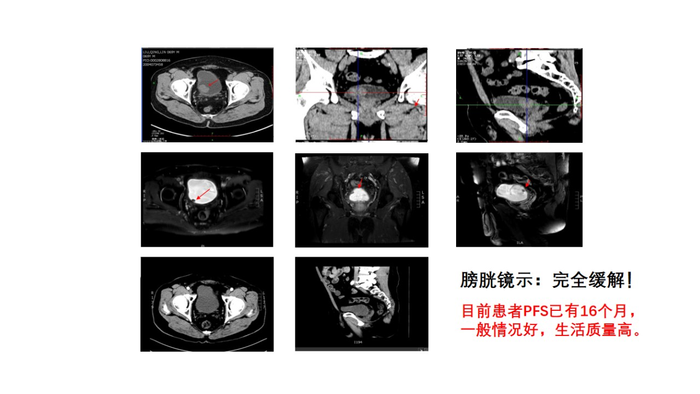

检查后核磁共振显示: 膀胱右后壁可见不规则肿物,约30*20mm大小,浸润肌层可能性大,盆腔未见肿大淋巴结。全身PET-CT显示:1.膀胱肿瘤电切术后改变,膀胱内不规则糖代谢显著增高的高密度影,考虑肿瘤残留。

TURBT+化疗+放疗的经典三联保膀胱综合治疗方案(TMT)之后,王先生的复查结果显示核磁共振: 膀胱充盈良好,膀胱壁均匀稍增厚。膀胱右后壁见宽基底与膀胱壁相连并凸入腔内结节影,12*7mm大小增强扫描明显强化。膀胱周围及盆腔淋巴结无肿大膀胱镜示完全缓解,目前王先生已经16个月没有复发,一般情况好,生活质量高,已经恢复了正常的工作和生活。